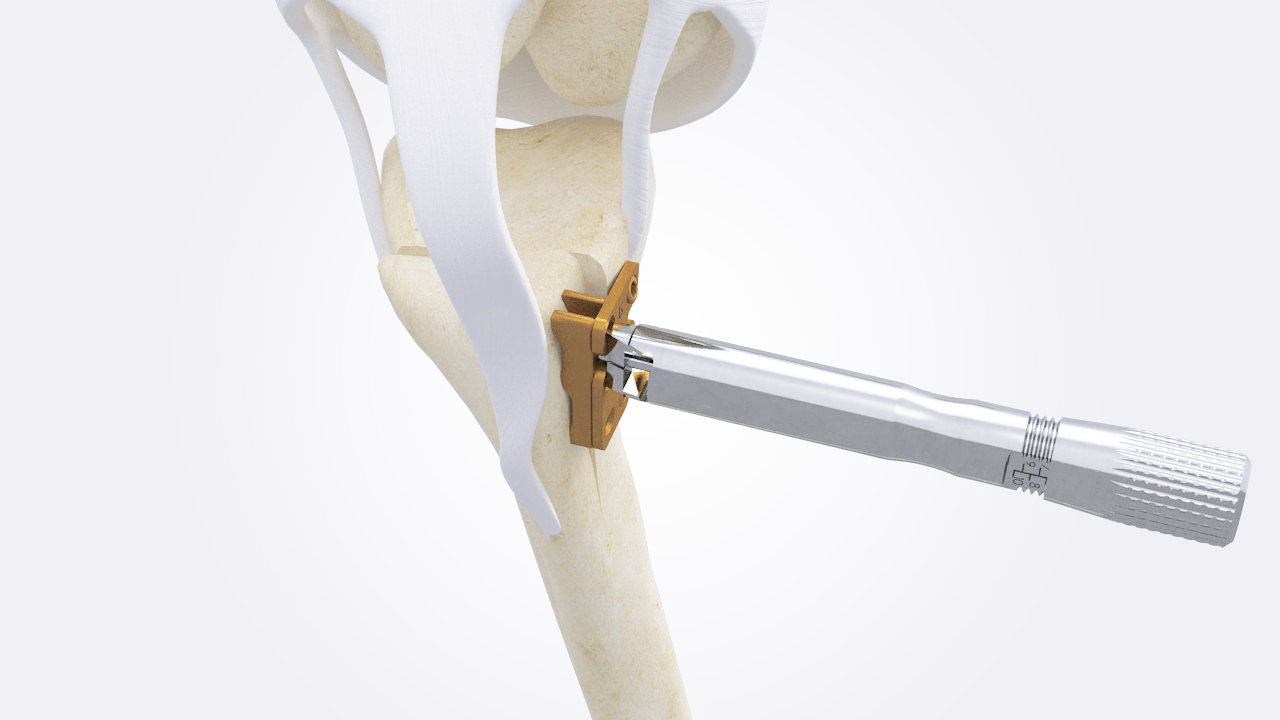

Testing the Stifle during Surgery

Enhancing surgical accuracy by allowing assessment of the stifle joint during surgery.

The uniquely designed Tibia Tappet facilitates precise adjustment of the tibial tuberosity. This allows surgeons to achieve precise positioning and conduct a thorough functional assessment before proceeding with screw fixation. Once the desired position is attained, fixation is carried out using the patellar spacer and screws, ensuring stability and alignment of the joint.